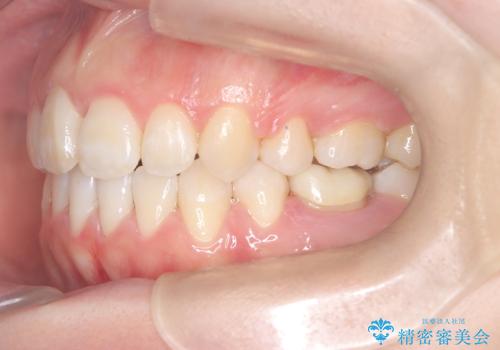

前歯のデコボコと開口を改善し、美しい口元へ

今回の矯正治療では、歯が並ぶスペースを確保するため、上下左右の小臼歯を抜歯しました。装置には目立ちにくい審美ワイヤーを使用し、見た目に配慮しながら治療を進めました。抜歯によってできたスペースを利用して歯を並べ、前歯のデコボコを解消。同時に、歯列全体を動かすことで、上下の歯がきちんと閉じる開口も改善しました。治療期間は約2年間。治療の結果、コンプレックスだった前歯のデコボコと開口が解消され、整った美しい歯並びと、しっかり咬める機能的な咬み合わせを獲得していただけました。